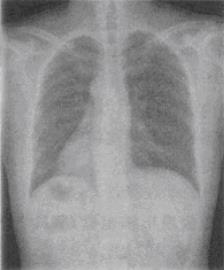

- 单项选择题 24岁女性,无明显症状,检查胸片如图所示。最可能的诊断是()。

A、镜面型右位心

B、右旋心

C、左旋心

D、中位心

E、内脏旋转不良

- A